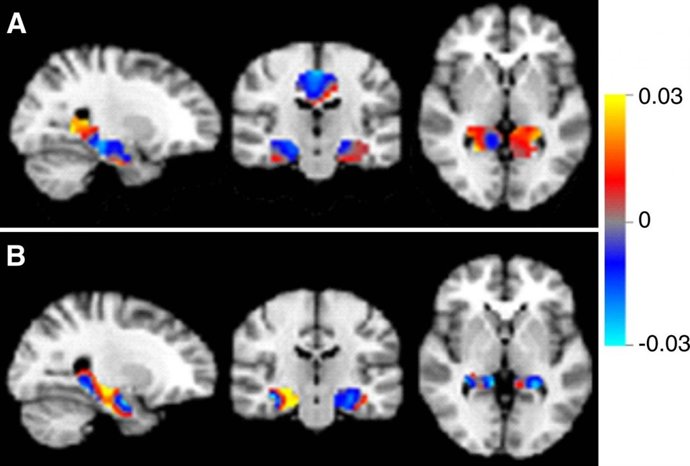

En concreto, esta terapia experimental ha conseguido reducir las placas de proteína tipo beta-amiloide vinculadas al Alzheimer, "lo cual supone un importante paso para el tratamiento de esta enfermedad", según el estudio publicado en Nature.

La investigación señala que esta terapia disminuye la cantidad de proteínas beta-amiloide localizadas en el cerebro de los pacientes con la enfermedad desarrollada de manera leve. Los depósitos de estas proteínas en el cerebro, según los estudios, desempeñan un papel clave en el desarrollo de los síntomas.